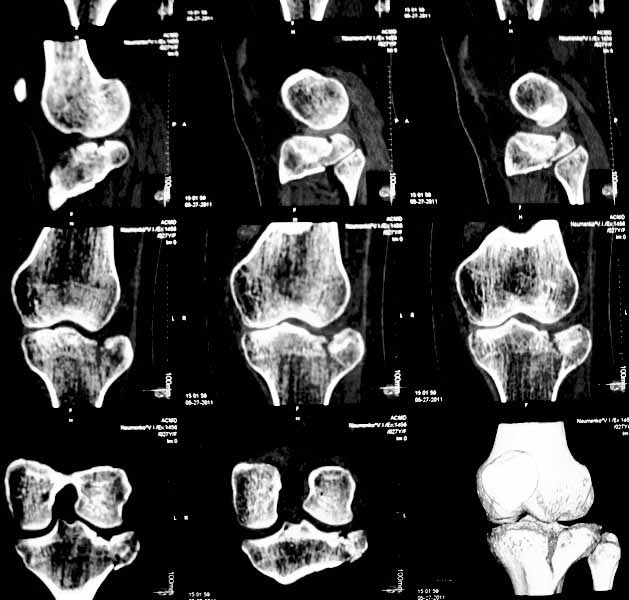

Уважаемые коллеги. Хочу представить вам клинический случай и получить информацию в отношении тактики лечения данной пациентки. Возраст 27 лет, парапланеристка, получила травму в Индии 28 апреля 2011г, упала с мотоцикла, получила боковой удар по левому коленному суставу.

Первая помощь оказана в индийской клинике, установлен диагноз - Ссадины левого локтевого сустава, левого плеча, левой и правой стоп, повреждение связок левого коленного сустава (не указано каких). Со слов пациентки выполнены рентгеновские снимки голени (их не отдали). Наложена циркулярная рассеченная скотч-каст повязка без захвата стопы на левую ногу, рекомендовано консервативное лечение со сроком иммобилизации 6 недель. Пострадавшая оставалась в Индии и вернулась 17 мая.

26 мая обратилась ко мне за консультацией с вопросом – можно ли снять иммобилизацию немного раньше и начать ходить без костылей?. СКТ – снимки прилагаю.

-клинически – вальгизация коленного сустава, умеренная сглаженность контуров сустава, постиммобилизационная контрактура сустава, медиальной и латеральной нестабильности сустава нет.